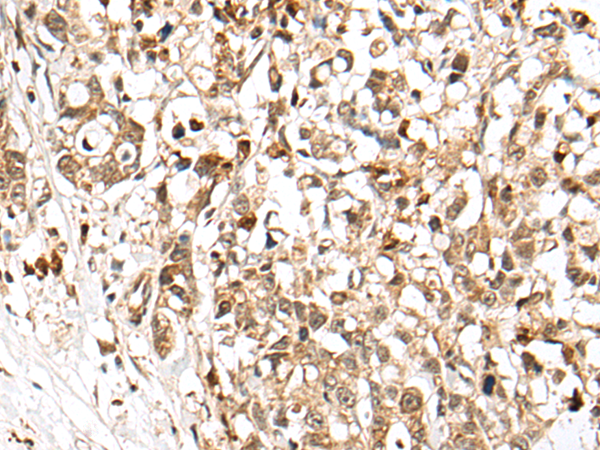

IHC (Immunohiostchemistry)

(The image on the left is immunohistochemistry of paraffin-embedded Human ovarian cancer tissue using 46677(SPRTN Antibody) at dilution 1/65, on the right is treated with fusion protein. (Original magnification: x200))